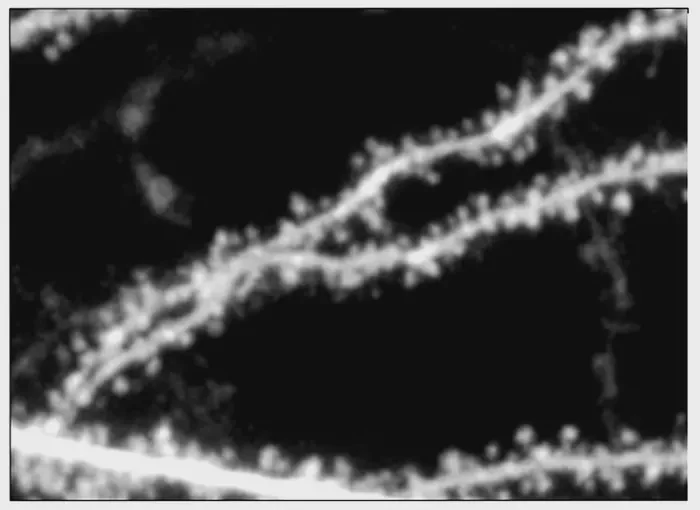

This current investigation builds on these prior discoveries, utilizing the insights on NMDA receptors to dissect their contributions to synaptic functions in a sophisticated manner. The pivotal component of this research was the molecular subunit known as GluN2B. The team identified that altering this specific receptor subunit altered the dynamics of protein synthesis and synaptic structure. By examining the genetic contributions of GluN2A and GluN2B, they determined that while both are essential for triggering synaptic plasticity, it is the GluN2B subunit that uniquely governs the physical structure of dendritic spines. This is a significant revelation, as it pinpoints a potential target for therapeutics aimed at reversing the symptoms of fragile X syndrome.

Researchers employed advanced genetic manipulation techniques to selectively inactivate the two different subunits of NMDA receptors in their model organisms. Their findings were illuminating; the absence of the GluN2B subunit alone caused alterations in spine morphology, indicating its unique role in determining synaptic structure. This contrasts sharply with GluN2A, which, when knocked out, did not affect spine size. This dissection of the NMDA receptor components offered a deeper understanding of how disruptions in these proteins can lead to conditions such as fragile X syndrome.

To further investigate the signaling pathways governed by the GluN2B subunit, the researchers turned their attention to its carboxy-terminal domain (CTD). The CTD is integral to how the receptor communicates within the cell, influencing downstream effects like spine morphology. Experimental manipulation revealed that modifications to the CTD of GluN2B can completely obliterate its influence on spine structure, thereby emphasizing its role in mediating important cellular functions.